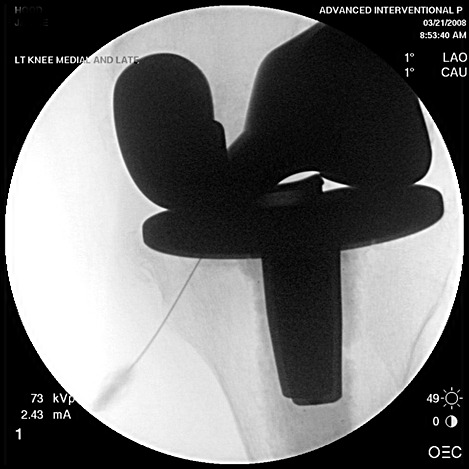

Above: Collapsed artificial knee joint also known as collapsed or failed knee arthroplasty treated at Advanced Interventional Pain Center with long term pain relief. Right: Patient with artificial hip joint with a lot of pain due to secondary chronic degenerative arthritis that has grown around the hip arthroplasty. Despite having an ineffective hip replacement, this patient after being treated at Advanced Interventional Pain Center received long term pain relief and improvement in function. Note that individual results will vary. Call 727-474-6507 to make appointments. Our e-mail: referrals@inter-pain.com